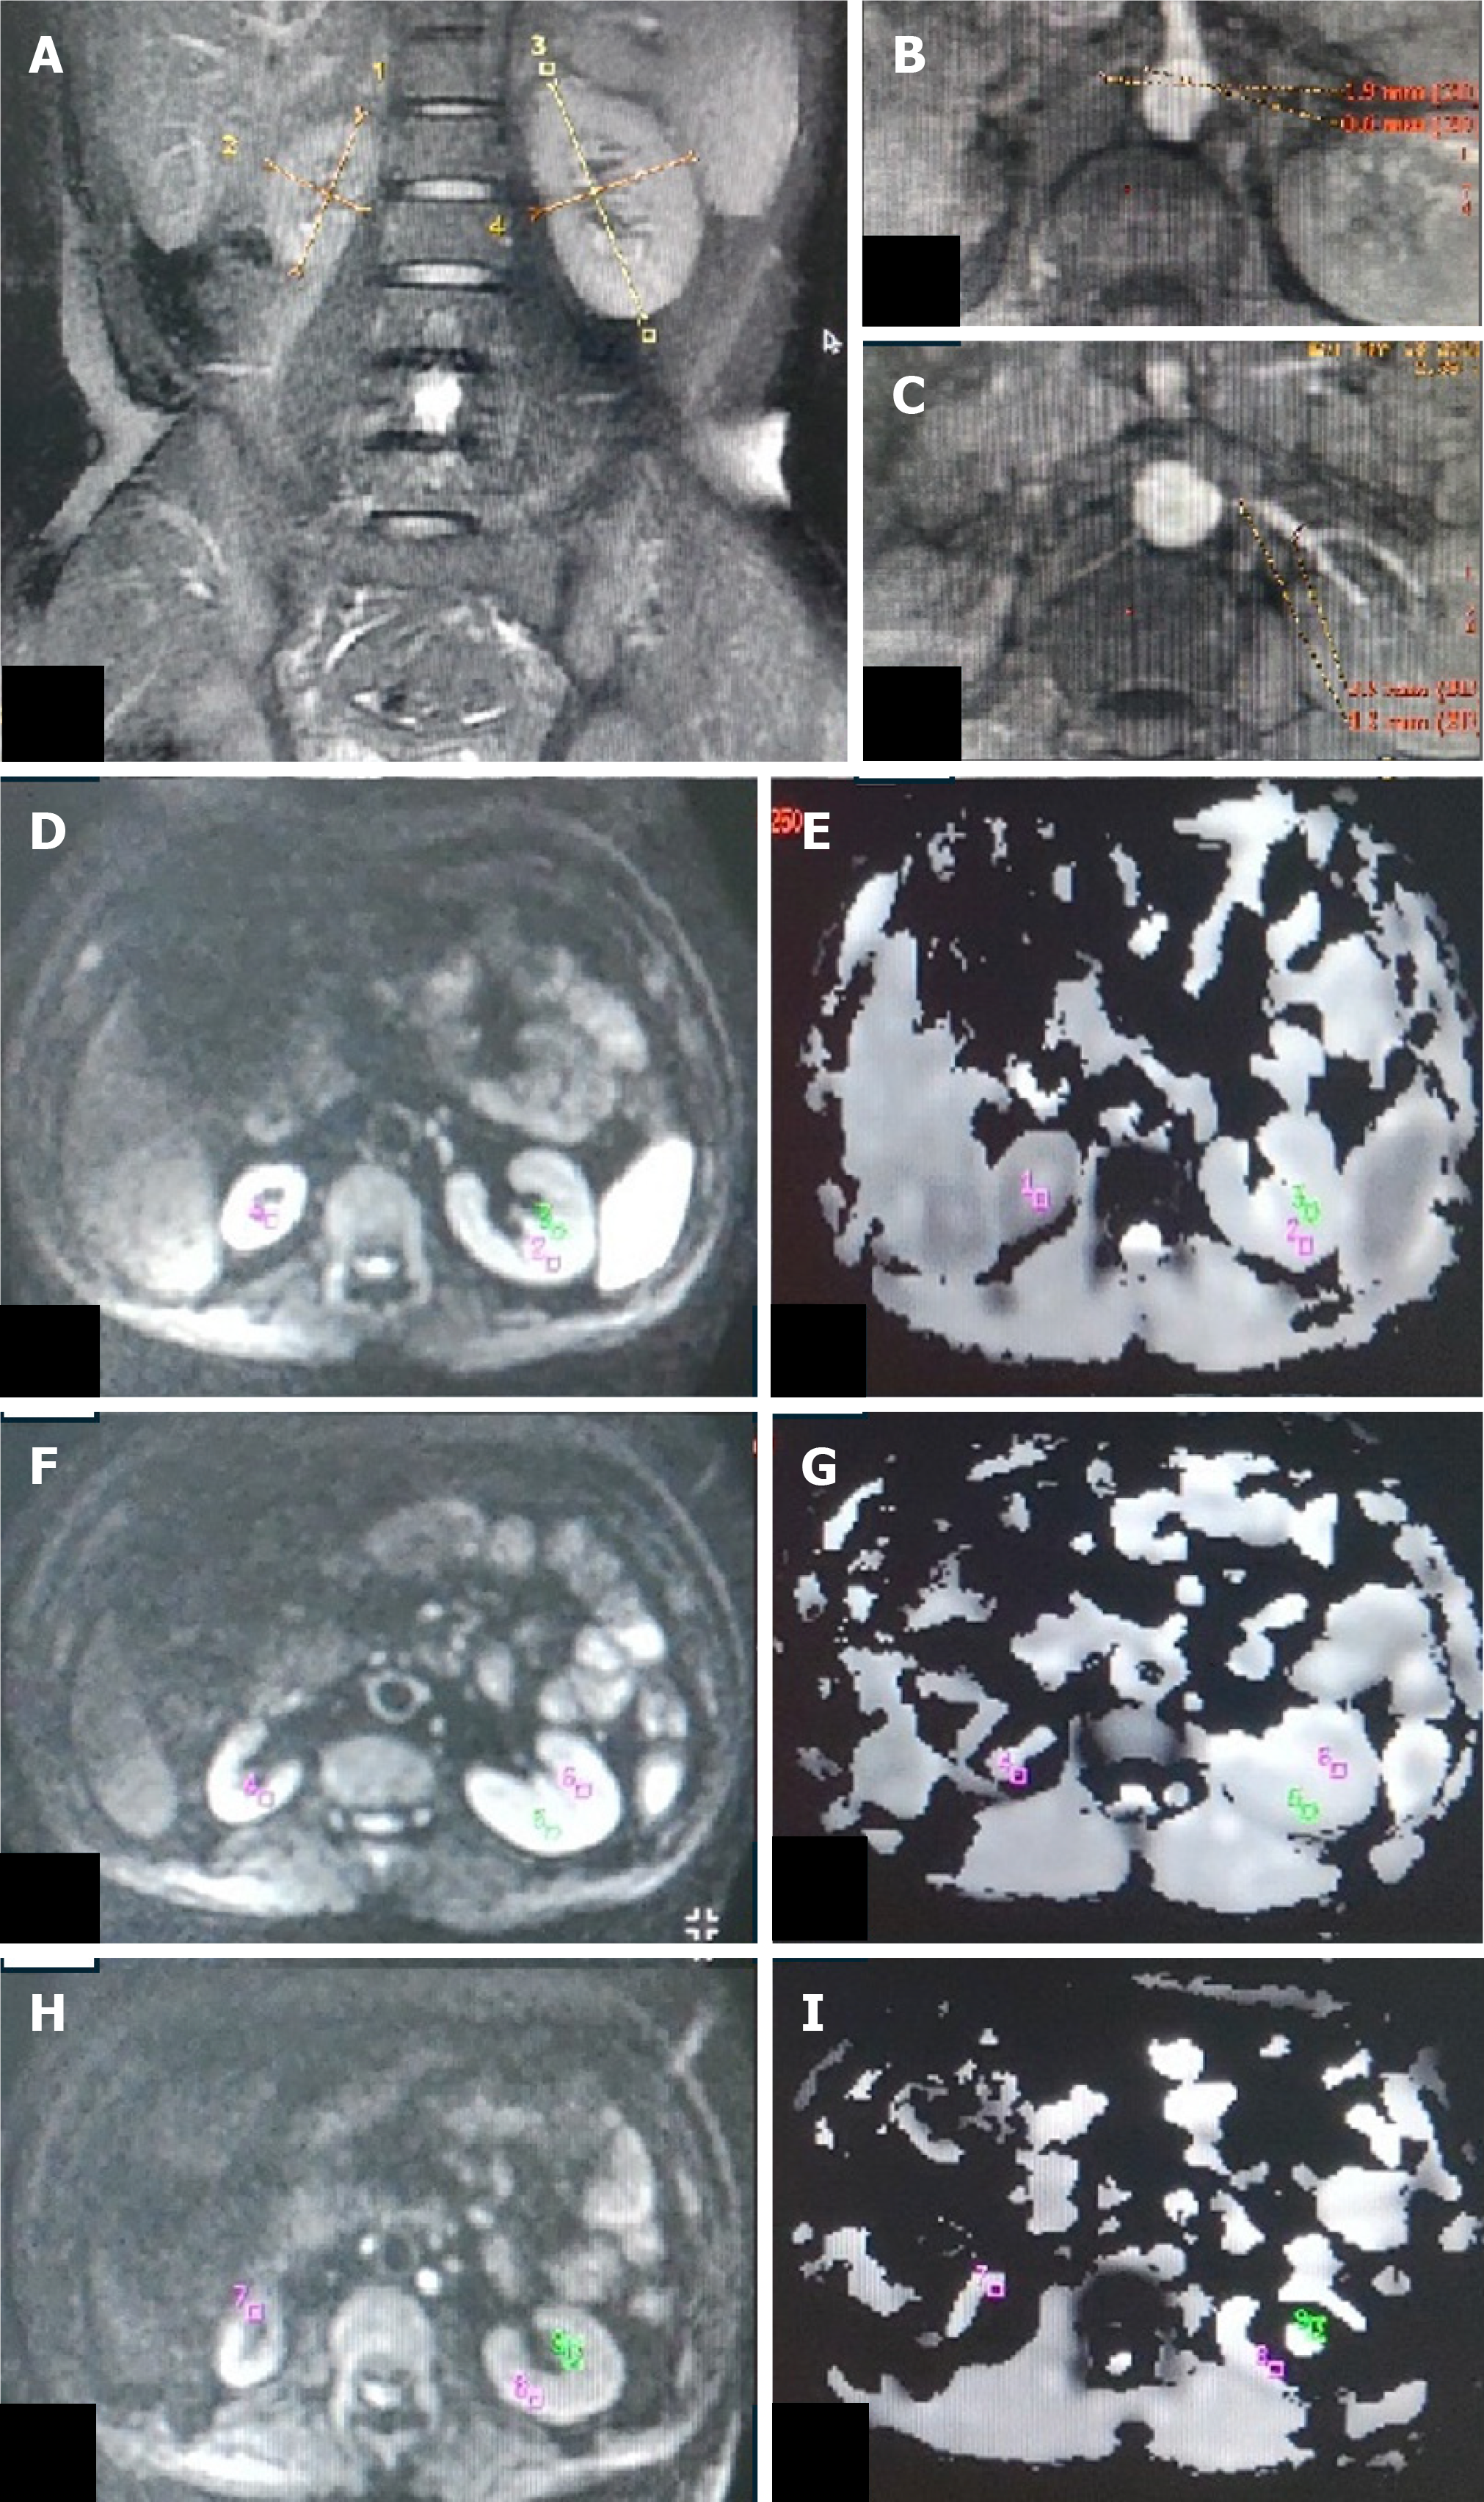

Figure 3 Unilateral renal artery stenosis with small-sized kidney.

A: T2W magnetic resonance image (MRI) (coronal plane) showing atrophic right kidney (4 cm) and normal-sized left kidney (9.4 cm); B: Non-contrast MR angiography (INHANCE) in axial plane depicting diffuse stenosis of right renal artery; C-J: DW MRI image (C, E, G, I) in the axial plane with corresponding apparent diffusion coefficient (ADC) map (D, F, H, J) of bilateral kidneys showing manually drawn region-of-interest (ROI) placed in the upper (C, D), middle (E, F) pole of bilateral kidneys, lower (G, H) pole region of right kidney and lower (I, J) pole region of left kidney. On the right side, as the kidney is atrophic, the ROI was placed in the corticomedullary region, whereas on the left, the ROI was placed separately in the cortex and medulla. Mean corticomedullary ADC of the right kidney was 1.43 × 10-3 mm2/s. Mean cortical ADC and medullary ADC values of the left kidney were 194 × 10-3 mm2/s and 1.91 × 10-3 mm2/s, respectively.